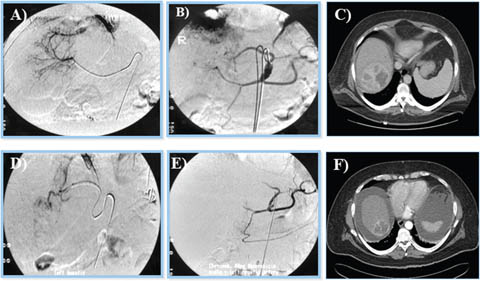

Trans-arterial chemoembolization

TACE is currently the standard of care for patients with intermediate–stage HCC with preserved liver function (7880). TACE is useful for patients that have a Child-Pugh score A or B with tumor diameter of >4 cm or four or more tumors as well as those with single tumor in which it is challenging to carry out liver resection or locoregional therapies as a result of systemic co-morbidities or anatomical limitations (81). TACE takes advantages of the dual arterial and portal venous liver parenchymal blood supply with preferential arterialization not only in cirrhotic liver but of HCC. It involves the selective arterial embolization with a gelatin mixed with lipiodol (a radiopaque contrast agent) with or without chemotherapy (doxorubicin, cisplatin or mitomycin C), into the tumor’s feeding blood vessel (66). The blockage of the arteries supplying the tumor results in tissue necrosis (Figure 10) (68, 79). In practice, TACE is a recommended therapy for patients with unresectable HCC, nonvascular invasion or disease outside the liver (64). TACE can also be used with drug-eluting beads (DEB-TACE) and evidence exists that patients who are on DEB-TACE treatments for unresectable HCC have better performance in comparison to those on conventional TACE (66). In addition, TACE is being used for the downstaging of tumors in association with systemic therapy or as bridge for transplantation.

Fig 10

Figure 10. Trans-arterial chemoembolization of the liver for hepatocellular carcinoma. A and B. Selective arterial embolization of the vessels feeding the tumor in the liver. C. Tumor visualized by CT scan. The procedure is performed with or without chemotherapy. D and E. After embolization, angiography showed obliteration of feeding vessels with shrinkage of the tumor. F. Follow up CT scan after embolization. Note an increase in patient’s ascites.